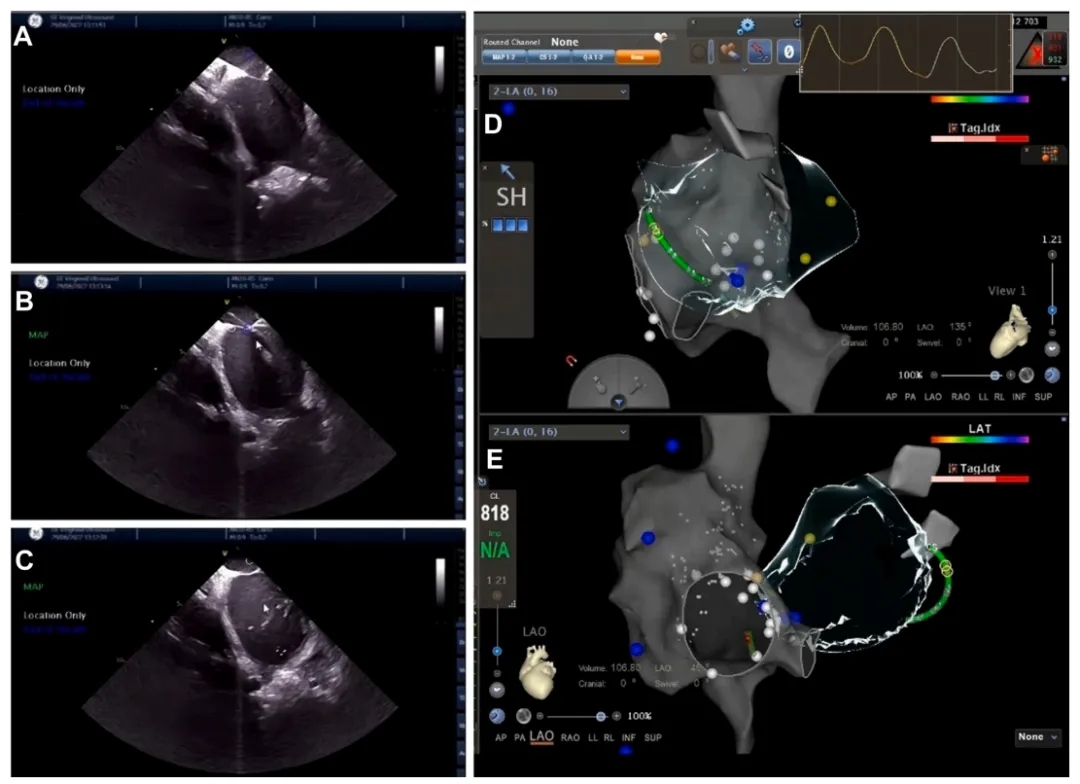

➤ 通过CARTO三维标测系统将ICE与三维电解剖标测(EAM)系统相结合,零射线下成功进行心包穿刺术。

(A)ICE 提示穿刺针在房间隔顶出“帐篷征”;(B)房间隔穿刺在实时ICE引导下进行;(C)穿刺针成功进入左心房,注入盐水确认;(D 和 E)EAM对右心房、腔静脉和房间隔进行详细重建。

➤ ICE引导下划定心包边界。

(A)左心室心尖近间隔侧;(B)左心室心尖;(C)左心室侧壁;(D)左心室游离壁;(E) 左心室心尖。

1)腔内超声平面;2)右前斜位;3)左前斜位。